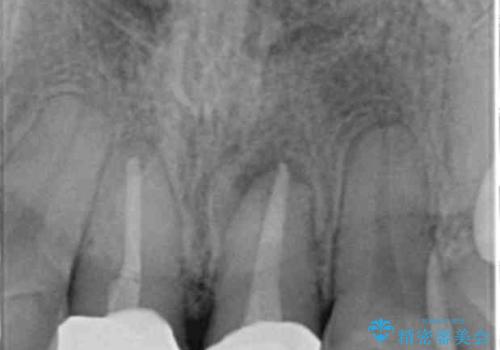

歯ぐきを押すと痛い、うずく、響く、などの症状は感染根管による根尖性歯周炎や歯の破折の所見であることが多々見られます。

今回は根尖性歯周炎に対する根管治療を行ったことで症状は改善し、快適に食事ができる状態へと改善しました。